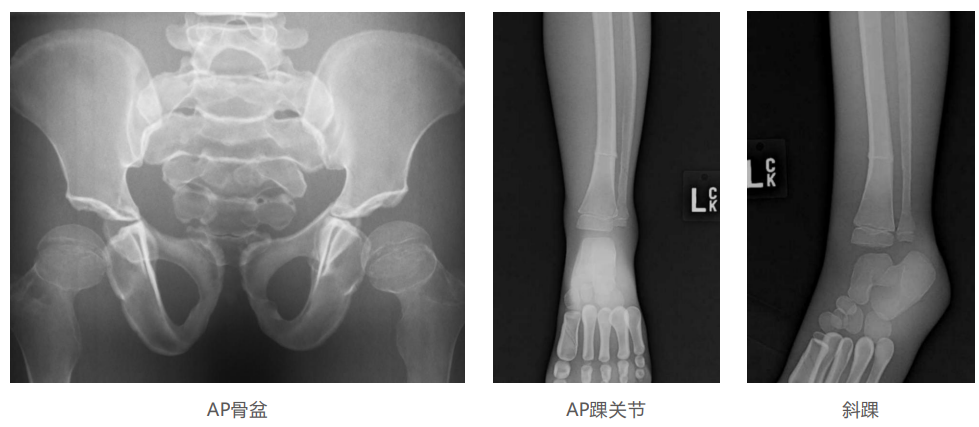

模體的大小和結(jié)構(gòu)都代表了人體模體,使其便攜和易于定位。包括頭、胳膊和腿在內(nèi)的整個(gè)身體。該系列包括六個(gè)部分的模體可單獨(dú)或作為一個(gè)完整的集合。

右肢有伸直或彎曲兩種配置。左臂和左腿可選伴有或不伴有內(nèi)嵌骨折。

骨折版本包含最常見的人體骨折類型 ,包括脛骨扣帶骨折和腓骨普通骨折;

第一跖骨骨折;橈骨切開復(fù)位骨折 ,第二中間趾骨常見骨折。組件由適當(dāng)?shù)木郯滨ズ铜h(huán)氧材料制成,模擬人體組織的X射線衰減特性,用于診斷和治療能量范圍(50 keV - 25 MeV) 。 材料經(jīng)久耐用 ,耐沖擊,適合連續(xù)搬運(yùn)。透明的軟組織有助于解剖標(biāo)志的視覺指示。